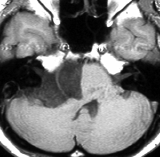

20代の女性が右の激しい顔面痛(三叉神経痛)で発症しました。左から順にMRIのT1強調画像,T2強調画像,拡散強調画像です。髄液と同じように見えますので脳の形の変形だけで腫瘍があることを疑います。でも,拡散強調画像では真っ白になるので腫瘍が存在していることがわかります。三叉神経は腫瘍の真ん中にあって伸びています。

術後の写真です。普通のMRIでは全部取れているかどうかわかりませんが,左の拡散強調画像をみるとおよそ全部取れていることがわかります。でも完全摘出の完全な証明は画像ではできません。術後10年くらい経ちますが再発はありませんでした。